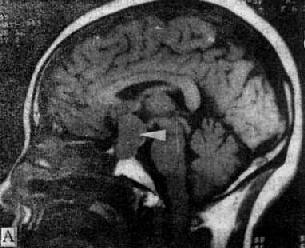

图5-1-6 MRI扫描SE序列图像 在矢状面(A)和冠状面(B)T1WI可见垂体肿块向鞍上延伸,呈等信号区(→);在横断面T1WI(C)和T2WI(D)上分别可见左枕和右基底节区脑梗塞灶呈低和高信号区(→);在矢状面T1WI(E)和横断面T2WI(F)上,可见基底动脉瘤环形影,其内为低信号和高信号区,高信号区为瘤内血栓形成(→) 七、颅内感染 颅内感染的病种很多,包括化脓性、结核性、病毒性和感染,以及脑寄生虫病。 (一)化脓性感染 化脓性脑膜炎早期CT扫描常无异常发现,脑膜粘连可出现脑室积水。并发硬膜下或外积脓时,在脑凸面或大脑镰旁可见新月形或梭形低密度灶,脓肿壁明显增强。脑脓肿早期CT表现为边缘模糊的低密度灶,伴有占位效应,代表急性脑炎期。脓肿形成期在大片低密度区内可见等密度环,壁薄和均匀性环形强化;产气杆菌感染,脓腔内可出现气泡或液面。CT可明确脓肿的部位、大小、数目和多房性;协助脓腔穿剌引流,并动态观察其发展和演变过程。目前脑脓肿的死亡率已由过去的36%~53%下降接近为零,这是由于CT的早期诊断和精确定位,配合临床及时准确治疗的结果。 (二)结核性感染 结核性脑膜炎的脑底渗出或肉芽增生,在CT上可表现为脑底池广泛或局灶性增强。结核瘤则出现等或混杂密度灶,可有钙化,均匀或环形强化。 (三)病毒性感染 单纯疱疹病毒性脑炎,CT表现为颞区低密度灶,边界模糊或清楚,占位效应轻,无增强。散发性脑炎可由多种病毒感染引起,CT上显示脑内散在性低密度灶,有时CT扫描阴性。 (四)真菌性感染 自然界普遍存在着真菌,当机体免疫或能低下时,常易罹患真菌感染,常见者有新形陷球菌、毛霉和茀状菌等。CT表现为脑炎、脑膜炎、肉芽肿、囊肿、脑出血或脑梗塞。真菌性肉芽肿呈等或高密度灶,灶周有脑水肿,增强CT呈大小和数目不等的强化结节,类似脑转移瘤的CT改变。 (五)脑寄生虫病 脑囊虫病典型CT表现为多发性小囊,囊壁或囊内的致密小点代表虫体的头节;散在性小圆形钙化点则表示死亡变性的囊肿;有时二者同时存在提示重复感染。脑血吸虫病急性脑炎型CT表现为低密度脑不肿区;慢性肉芽肿型则表现为强化结节,其形状、大小和数目不一。脑包虫病CT表现为巨大脑内囊肿,边界清楚,CT值类似水,周围无水肿。 CT扫描阴性的颅内感染性疾病例如脑膜炎和病毒性脑炎等,MRI常可获得进一步的证实。 八、其他脑疾病 (一)变性脑病 大脑变性脑病常见的老年性痴呆和多发脑梗塞性痴呆,CT扫描可见幕上脑室普遍性扩大,脑沟增宽,对称或非对称性,血管性痴呆尚可见多发性新老梗塞灶存在。 小脑和脑干变性疾病常见的有橄榄-脑桥-小脑萎缩和Marie共济失调,CT显示第四脑室扩大,小脑上沟增宽,后颅凹脑干周围脑池扩张。 基底节变性疾病有Wilson病、Parkinson病和CO中毒等,CT上显示脑室扩大以侧脑室前角扩大为明显,脑底池和外侧裂池增宽,脑基底节区有时可见对称或非对称性低密度灶。 (二)脱髓鞘脑病 先天性髓发育不良或称为脑白质营养不良,可见于异染性脑白质营养不良、类球状细胞白质营养不良、肾上腺脑白质营养不良等。CT表现脑白质对称性密度减低,与脑皮质的对比鲜明。获得性髓鞘脱失又称为脑白质病,常见有多发性硬化和皮质下小动脉硬化性脑病等,CT表现为脑室周围散在性斑片或带状低密度灶,伴有程度不同的脑萎缩。 (三)先天性畸形 脑膜(脑)膨出CT可见颅骨缺损,自缺损处突出一液性软组织包块,有的包块内有脑组织。胼低体发育不全显示双侧侧脑室扩大并分离,第三脑室扩大向上前移位于分离侧脑室之间,有的合并脂肪瘤或囊肿。Chiari畸形上CT可见小脑扁桃体下疝;有时伴有脑干、小脑和第四脑室延长下疝及脑积水改变,可合并脊髓空洞症、脑膜膨出及其他脑脊髓畸形。 (四)新生儿脑病 新生儿窒息CT可见弥漫性脑水肿、颅内出血或脑室内外积水。新生儿颅内出血由于产伤或缺氧所引起,出血于硬膜下或硬膜外腔、蛛网膜下腔、脑和脑室内,而以室管膜下出血具有特征性,CT表现沿脑室壁出现高密度线形影,后期遗留交通或非交通性脑积水。 MRI对许多变性脑病、脱髓鞘脑病和先天性畸形能够比CT提供更多的信息资料,可作为CT扫描诊断的补充。 九、脊柱和脊髓疾病 (一)椎管狭窄 椎管狭窄分为骨性和软组织狭窄,骨性椎管狭窄又分为中心型狭窄和周围型狭窄,后者指侧隐窝和椎间孔狭窄。先天性椎管狭窄常伴发于骨发育不全;获得性椎管狭窄可由骨折、炎症、肿瘤和退行性变引起,临床上出现一系列脊髓、脊神经和营养血管的压迫症状。横断面CT扫描可直接观察椎管狭窄变形,测量椎管大小并探明引起椎管狭窄的病因。 (二)椎间盘脱出CT扫描可直接显示突出于椎管或椎间孔内的软组织块影,与椎间盘相连或游离于椎管内,硬膜囊受压变形,硬膜外脂肪层变薄或消失,脊神经根增粗或湮没。椎间盘性变性显示变扁变形,向周围膨出,或出现气体(直空现象)。MRI上显示更为清楚。 (三)脊髓疾病 脊髓损伤急性期可见脊髓出血、水肿、受压、移位、挫伤或断裂;慢性期可见脊髓软化、萎缩、囊变或空腔化。脊髓肿瘤位于髓内者多为星形细胞或室管膜瘤,髓外硬膜内者多为脊膜或神经纤维瘤,硬外肿瘤以转移瘤常见。脊髓造影配合CT扫描才能对椎管内肿瘤作出正确的定位诊断。先天性畸形常见有脊髓空洞症、脊髓纵裂和脊髓血管畸形等,后者需行增强CT扫描。可显示脊髓表面扩张扭曲的血管影,并能确定血管畸形在椎管内大致伸延的范围。 MRI的软组织分辨率比CT高,矢状面扫描图像上可直观地显示脊髓病变的全貌及与周围组织结构的关系,是当今诊断脊髓疾病的最佳选择。 (责任编辑:泉水) |